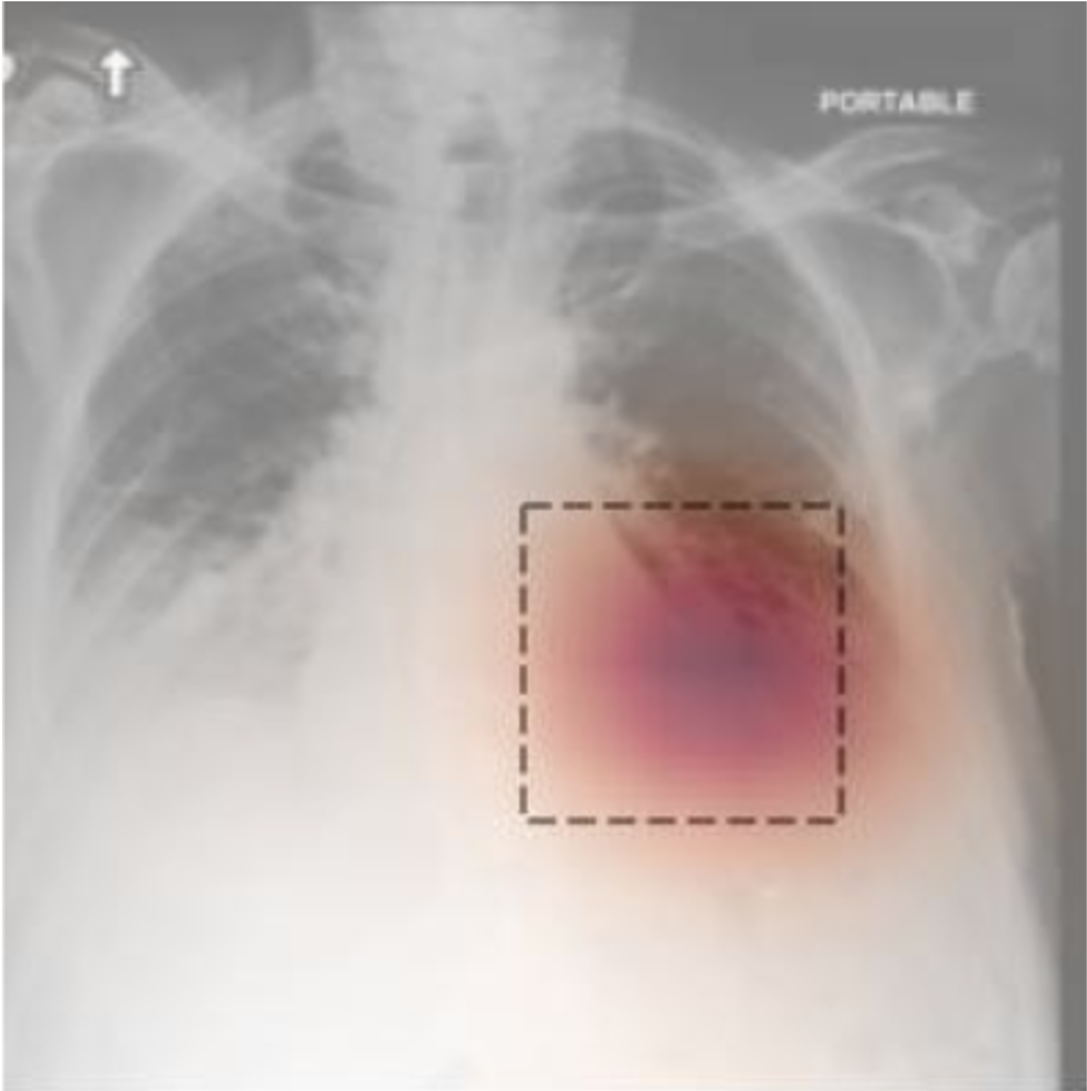

We conduct additional experiments to inspect the internal contribution of each module. We sequentially add each module to the model architecture to assess its impact. The averaged score of zero-shot and few-shot classification was reported in Table 4. Sentence-patch matching takes the most significant improvement by 2.267% since it can mine dense local supervision from data pairs. Moreover, with integrity estimation took the second place with 1.76% improvement, which reveals the importance of semantic complementness of image data in LIP. In addition, we provide the visualization of learned and a sample of the heatmap for a given prompt in Fig. 3. MLIP can accurately identify the related region in the image.